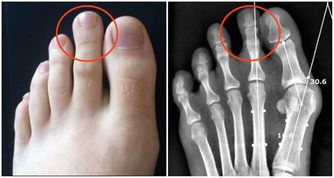

4、痛風患者

痛風的人都是有著高尿酸血,對於高脂的飲食是需要避免的,因為高脂飲食可能會導致尿酸排出的減少,從而可能會加重病情的,而花生中就含有大量蛋白質、脂肪,也屬於中等嘌呤含量的食物,特別是痛風急性發作期的時候,應該禁止食用花生的。